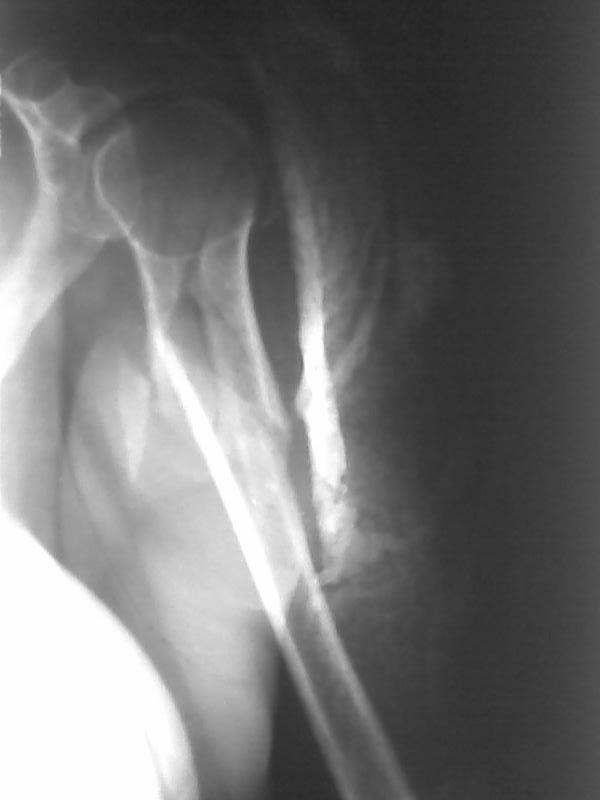

Здравствуйте уважаемые коллеги!!! Недавно стали применять в своей работе малоинвазивные методы лечения. На прошлой неделе прооперировали пожилую женщину с сопутствующим сахарным диабетом по поводу оскольчатого перелома в/3 плечевой кости штифтом PHN фирмы "Mathys". Имеется вот такое стояние костных отломков (см. рентгенограммы). Мнения коллег в отделении разделились: одни считают, что стояние отломков крайне неудовлетворительное и сращение кости при таком стоянии вряд ли возможно, другие считают, что при закрытом методе остеосинтеза и стабильной фиксации отломков результат будет благоприятный и сращение кости, даже при таком стоянии костных отломков, будет обязательно. Я придерживаюсь последнего мнения. Коллеги, каково ваше мнение? У нас это первые больные после подобных операций, поэтому большого опыта не имеем. Поделитесь своим опытом! И если это возможно, то для убедительности выложите рентгенограммы после операции и после сращения переломов с подобным стоянием отломков. Заранее СПАСИБО!!!

Высылаю рентгенограммы больной до операции и в гипсовой лонгете. Сейчас больную вообщем-то особо ничего не беспокоит, незначительная болезненность в области перелома при движениях плечом, первые два дня была отечность кисти, которая сейчас исчезла, объем движений в локтевом суставе постепенно увеличивается, отведение плеча пока небольшое. Дистальное блокирование выполнено одним винтом в передне-заднем направлении (через бицепс. Да, клинок мы конечно же заблокировали концевым колпачком. Нас тоже беспокоит возможность развития импиджмент синдрома, надеемся на то, что больная разработает движения в плечевом суставе.

Положение отломков диафиза приемлемое.

Уважаемый Евгений! Положение отломков благоприятно для сращения. Варусное смещение отломков можно было бы уменьшить изначально использовав более медиальную точку введения стержня. Импиджмент, скорее всего, будет, удаляйте стержень по-возможности раньше. Для лечения данного перелома можно было бы обратить внимание на ретроградный способ введения стержня, но к данной методике нужно подходить с осторожностью, необходим опыт БИОС.